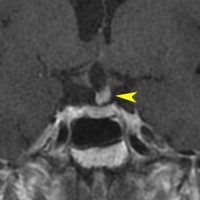

8歳で両側の視力低下が生じました。眼科では精神的なものと診断されて,4ヶ月くらいで右視力 0.4(耳側半盲),左指数弁となりました。のう胞性頭蓋咽頭腫で大きな骨化を伴うもので1月くらいの間に全盲になるかもと判断しました(失明寸前です)。

矢印の先に見えるように下垂体は正常の形態です。この画像から灰白隆起の左後方,乳頭体の前方が腫瘍発生母地ということがわかります。尿崩症もなく下垂体機能は正常です。経鼻的な内視鏡手術で腫瘍の大部分を摘出すれば下垂体機能は廃絶します。

とにかく失明を避けるために急いで経蝶形骨洞手術(transsphenoidal-transtuberculum sellae approach)で腫瘍のう胞の減圧をしました(緑の矢印の経路 by 函館中央病院加藤功先生)。その後に前頭開頭で腫瘍を全摘出しました(右側の画像)。尿崩症はでましたが下垂体前葉機能は正常です。

右視力 0.45,左明暗弁の視力が残りました。でももし,経鼻手術をしないでいきなり開頭すればおそらく全盲になっていた例です。